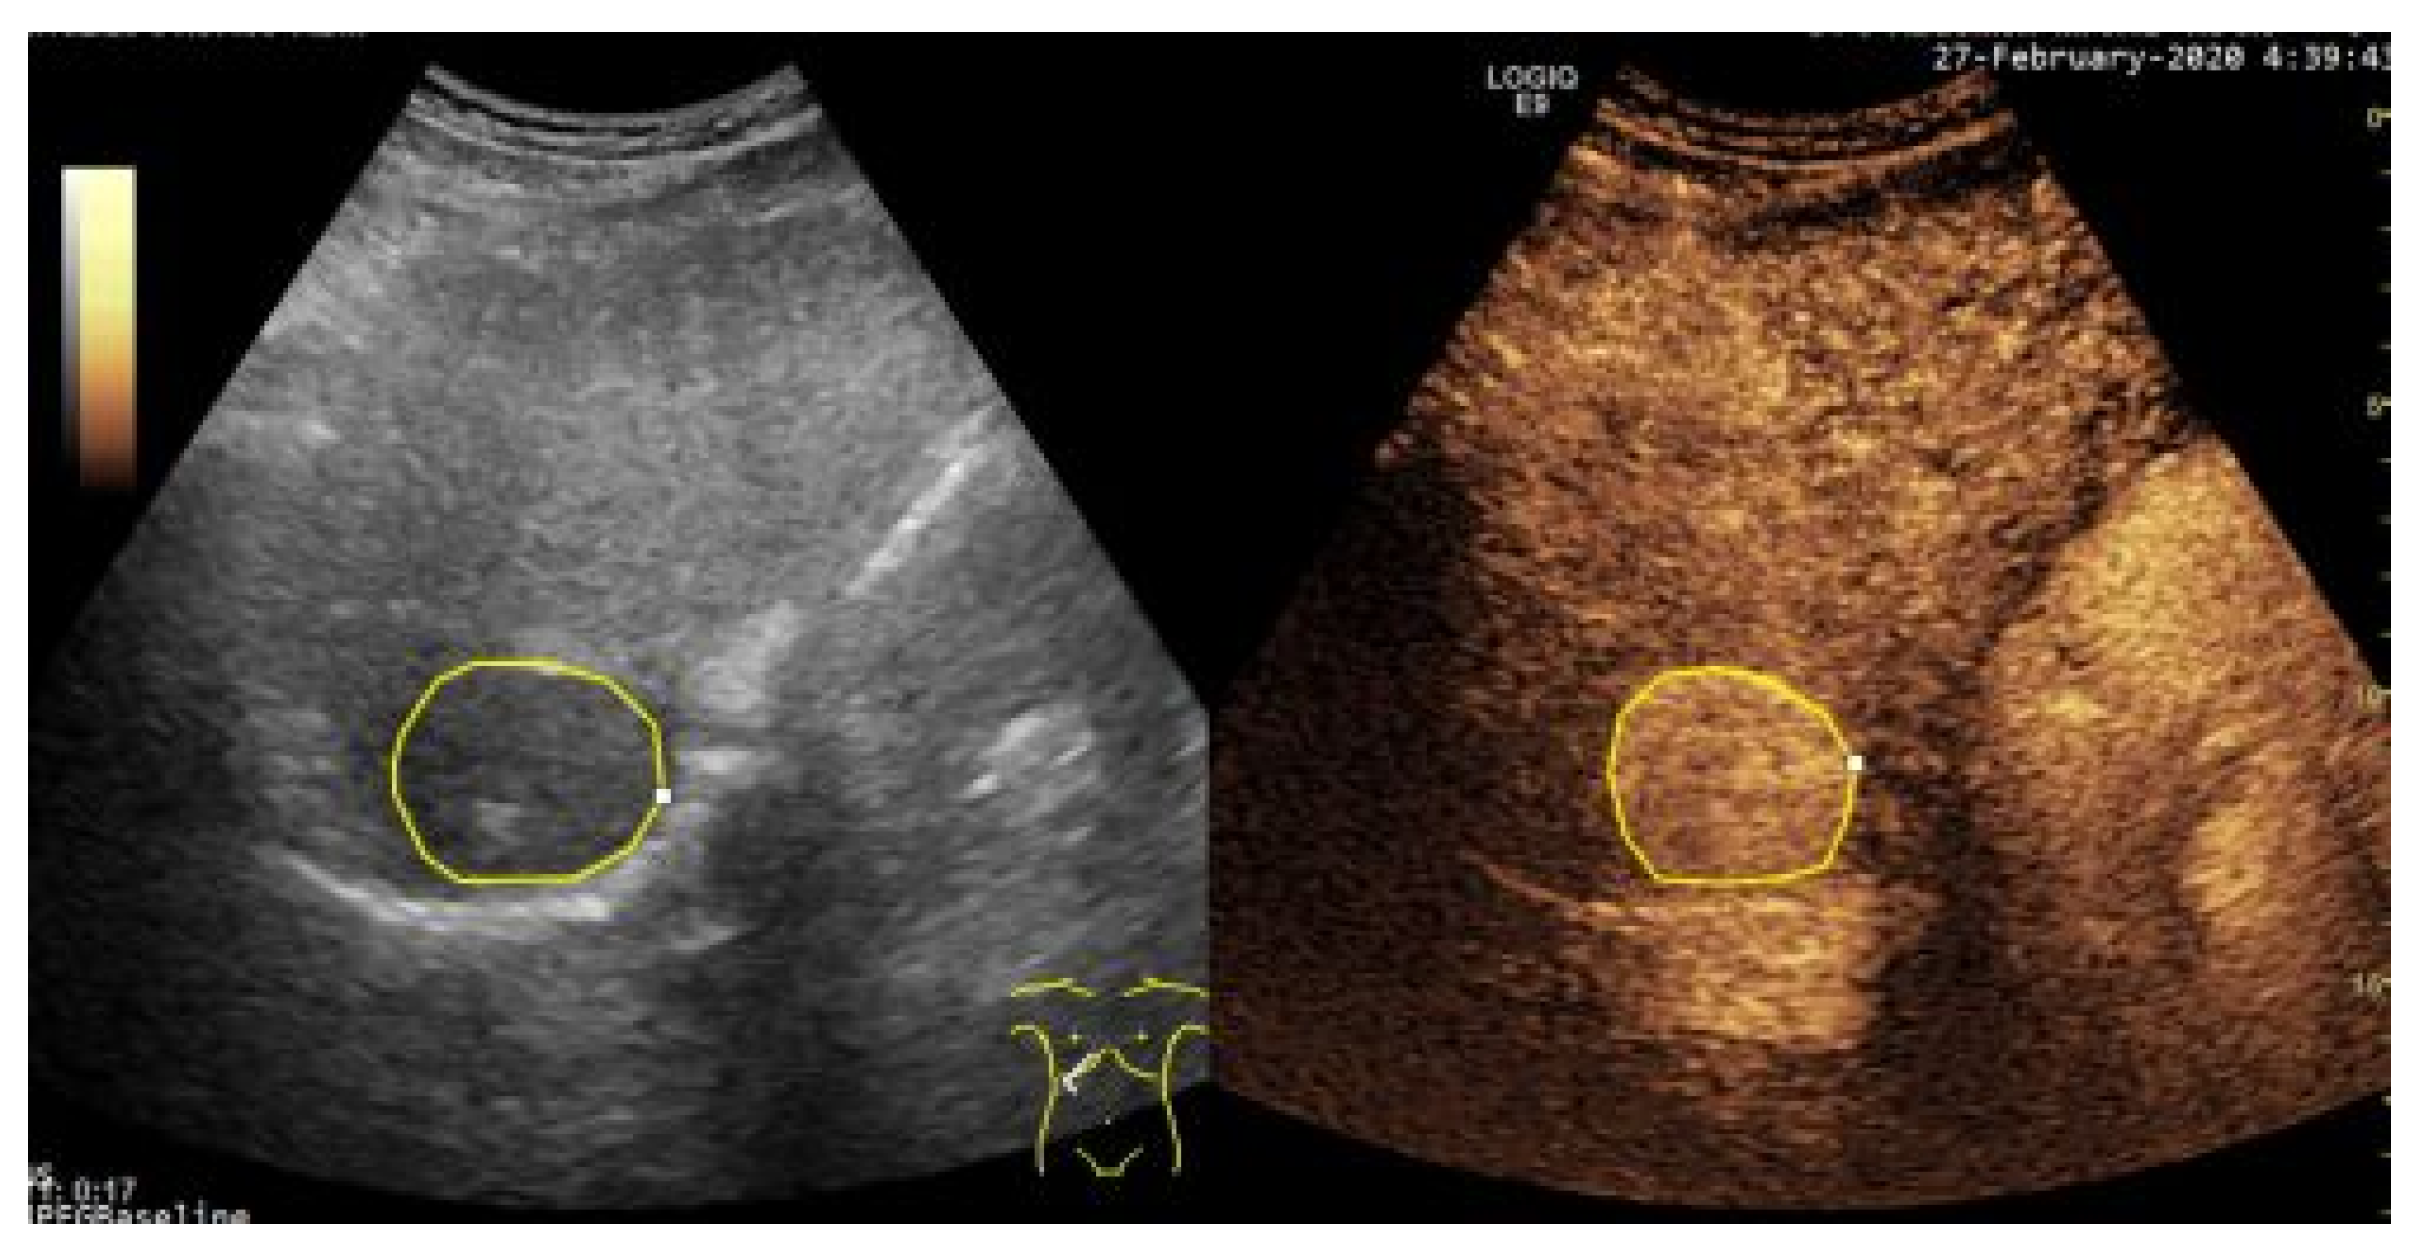

Within B-mode ultrasound images, focal, encephaloid HCC appears, in more advanced evolution phases, as a well-defined region, of 3–5 cm in size, being hyperechogenic and often heterogeneous, due to the interleaving of fatty cells, necrosis, fibrosis and active growth tissue [2]. In CEUS images, HCC appears more highlighted, due to the dense and complex vessel structure that is specific to the malignant tumors [3]. The HCC tumors are usually hyper-enhanced during the arterial phase, showing washout during the portal venous and delayed phases [5]. An eloquent example of HCC tumor, as it appears in a pair of B-mode Ultrasound and CEUS images, is depicted within Figure 1. However, in many cases, within both B-mode ultrasound images and CEUS images, HCC is hardly distinguishable from the cirrhotic parenchyma on which it evolves, so advanced computerized methods are due, in order to overpass the limitations of the human eye, in a non-invasive manner.

Figure 1.

Example of a Hepatocellular Carcinoma (HCC) tumor within B-mode Ultrasound (left) and Contrast-Enhanced Ultrasound (CEUS) images (right), delineated by an experienced radiologist.